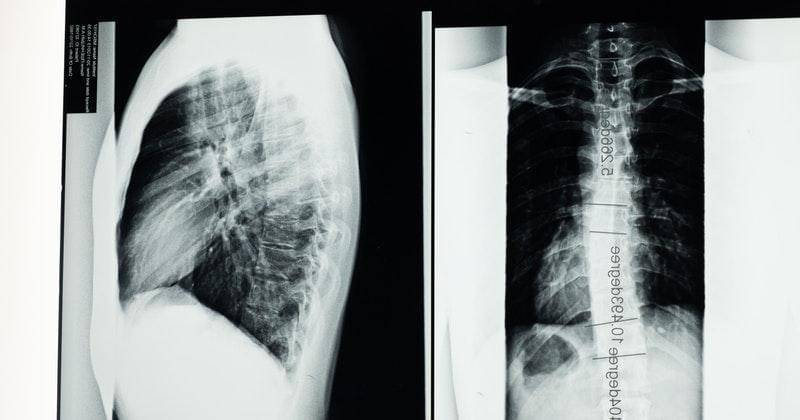

Paru-paru basah adalah istilah umum untuk sindrom gangguan pernapasan akut (ARDS). Kondisi ini terjadi ketika paru-paru diisi dengan banyak cairan dan bukannya udara. Paru-paru basah ini biasanya terjadi akibat infeksi pada paru-paru yang membuat paru-paru berisi cairan bisa darah infeksi hingga cairan cadangan dari paru-paru itu sendiri.

Kondisi paru-paru basah bisa menggambarkan beberapa penyakit, seperti pneumonia akibat infeksi bakteri atau virus (termasuk infeksi virus Corona atau Covid-19).

3. Gejala paru-paru basah yang umum terjadi

Ada beberapa gejala paru-paru basah yang bisa dikenali secara umum. Tanda yang paling sering dialami adalah flu berkepanjangan. Jika sampai mengeluarkan dahak hingga kemerahan (berdarah) jangan disepelekan ya, Ma.

Berikut adalah gejala penyakit paru-paru basah:

Paru-paru basah adalah masalah kesehatan yang perlu mendapat pemeriksaan dan penanganan dari dokter spesialis paru. Jika tidak ditangani, kondisi ini berpotensi menjadi semakin berat dan merusak paru-paru.

Beberapa orang dengan kondisi paru-paru basah atau pneumonia bisa menyebabkan nyawa tidak selamat. Pengobatan untuk penyakit ini disesuaikan dengan tingkat keparahan dan penyebabnya.